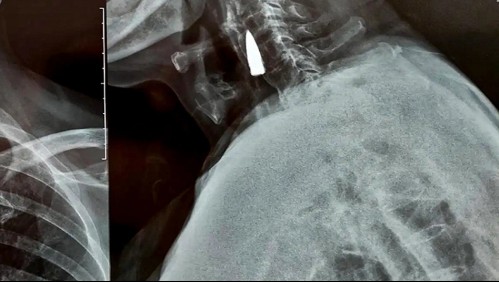

Mundo Veterano de guerra se somete a radiografía y descubre que tenía una bala incrustada en su cuello